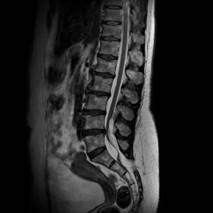

MRI(Magnetic Resonance Imaging/磁気共鳴画像)は、強力な磁石と電波を用いて体の内部を詳しく撮影する検査です。

放射線被ばくがなく痛みもない安全な検査です。通常20~40分程度で終わります。

脳だけでなく、全身のさまざまな部位の検査が可能です。

脳・脊椎・関節・四肢・腹部・骨盤・乳腺など幅広い部位に対応しています。

当院では最新の3テスラMRI装置を導入しており、従来の1.5テスラ装置とあわせて検査内容に応じた撮影を行っています。

3T MRIでは、高精細でより詳細な画像診断が可能です。